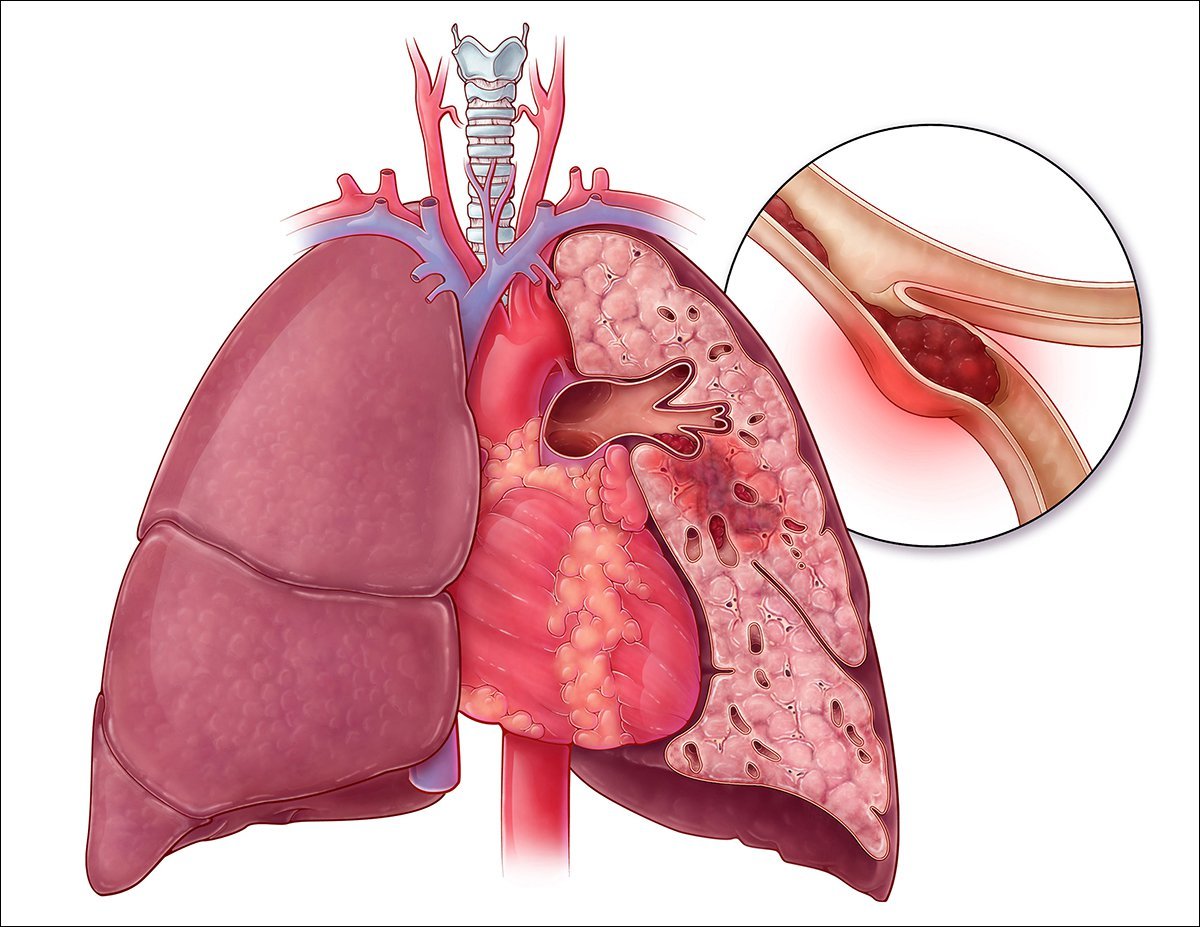

TROMBOEMBOLISMO PULMONAR

O que define um TEP maciço

Obstrução > 50% do leito arterial pulmonar

O que define um TEP Moderado-Grande

Obstrução 30-50% do leito arterial

O que define TEP Pequeno/moderado

Obstrução < 30% do leito arterial